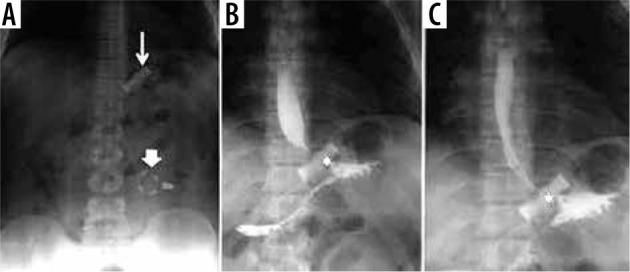

诊断性影像学在减重手术急性并发症诊断中的应用

Diagnostic imaging in the diagnosis of acute complications of bariatric surgery.

The aim of study is to identify the frequency of acute complications and imaging findings at gastro-intestinal transit (GI) and computerised tomography (CT) in a group of obese patients who developed clinical suspicion of acute complications (painful and meteoric abdomen, nausea, vomiting, fever, intestinal blockage) in post bariatric surgery.

MATERIAL AND METHODS

We retrospectively review 954 obese patients who underwent bariatric surgery between 2013 and 2019. The study included 72 patients who developed clinical suspicion of acute complications (painful and meteoric abdomen, nausea, vomiting, fever, intestinal blockage) within 6 days of bariatric surgery of sleeve gastrectomy, gastric banding, gastric bypass with Roux loop confirmed by CT, and who underwent a gastrointestinal transit before the CT examination.

RESULTS

GI exam allowed visualisation of 58% of complications. Analysing the data for each surgical technique, 46 post-operative complications were found involve gastric banding. The most frequent was bandage migration (26 cases, 56 %), identified in all cases at GI transit and then confirmed on CT.

CONCLUSIONS

The study suggests that CT should be used to clarify all doubtful or clinically discordant GI transit exam results. The participation of a radiologist in qualification and post-operative evaluation is important for bariatric surgery patients.

本研究旨在确定一组肥胖患者在接受减重手术后出现急性并发症临床疑似症状(腹痛、腹胀、恶心、呕吐、发热、肠梗阻)时,胃肠道造影(GI)和计算机断层扫描(CT)检查中急性并发症的发生率及影像学表现。

材料与方法

我们回顾性分析了2013年至2019年间接受减重手术的954例肥胖患者。该研究纳入了72例在袖状胃切除术、胃束带术、Roux袢胃旁路术后6天内出现急性并发症临床疑似症状(腹痛、腹胀、恶心、呕吐、发热、肠梗阻)且经CT证实,并在CT检查前进行了胃肠道造影的患者。

结果

GI检查能够发现58%的并发症。分析每种手术技术的数据,发现46例术后并发症与胃束带术有关。最常见的是束带移位(26例,56%),所有病例在GI造影时均被发现,随后经CT证实。

结论

该研究表明,对于所有可疑或临床结果不一致的GI造影检查结果,均应使用CT进行明确。放射科医生参与减重手术患者的术前评估和术后评估非常重要。